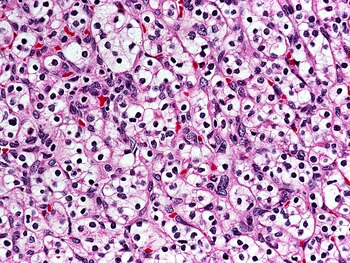

El cáncer de riñón, también conocido como carcinoma de células renales, es una de las diez formas más frecuentes de cáncer en hombres y mujeres.

En Argentina, representa uno de los seis tipos de tumores más comunes. Según datos de la Agencia Internacional de Investigación sobre Cáncer (IARC), cada año se diagnostican 4.908 nuevos casos en el país, lo que equivale a más de 13 diagnósticos diarios. Las proyecciones indican que para 2030 esta cifra podría aumentar un 18 % respecto de los registros actuales.